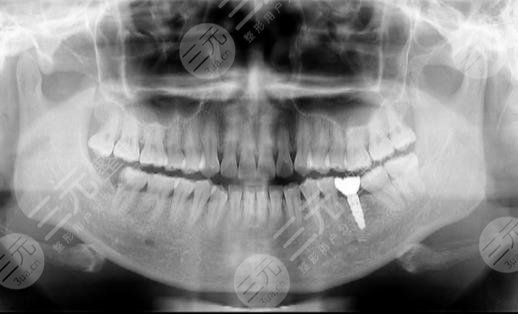

真没有想到,有一天自己也做了种植牙,因为在我的印象中总感觉做这只有中老年才做的事情,而我才36岁正值壮年,唉,但现在的嘴巴里竟然有一个假牙存在了。还是因为自己的一颗坏牙说起,我这个牙齿是在生完宝宝之后,那一段时间没有注意牙齿的护理,结果就有一个牙齿坏了,现在已经有差不多七八年的时间越坏越深。到医院之后医生说我的牙齿损坏的比较严重,对于其他的牙齿健康也会产生危险,所以建议我将牙齿拔了。一开始我并没有认识到事情的严重性,但真的将牙齿拔出来,我一下子就全蒙了。

将牙齿拔出来之后,现在我面临的就是镶牙和种植牙这两条路了。镶牙总体来说还比较便宜一些,但是使用感不好,牙齿的年限也比较少,对于我这样的年轻人来说,做种植牙才是更合适的。但是种植牙真的较为贵,让我较为的心疼我的钱包,较终我还是决定做种植牙,反正就一颗牙贵就贵吧。做种植牙的时候使用了麻醉药物,所以只听见一声拉开肉的声音,但的确没有感觉到疼痛,然后感觉很快就种植完成了。

现在已经使用了种植牙有半年的时间了,说一说我的感受吧,首先觉得是没有异物感,这一点我还是比较意外的,因为总觉得是假牙,怎么可能和真牙相比呢。而种植牙还是会有一定的塞牙情况,所以也每隔一段时间就需要做洗牙。在刚刚做种植牙的前几天,牙龈还是有些肿的,通过冰敷消肿还是挺快的。总结一句,那就是做种植牙挺好,只不过我的钱包受不了。